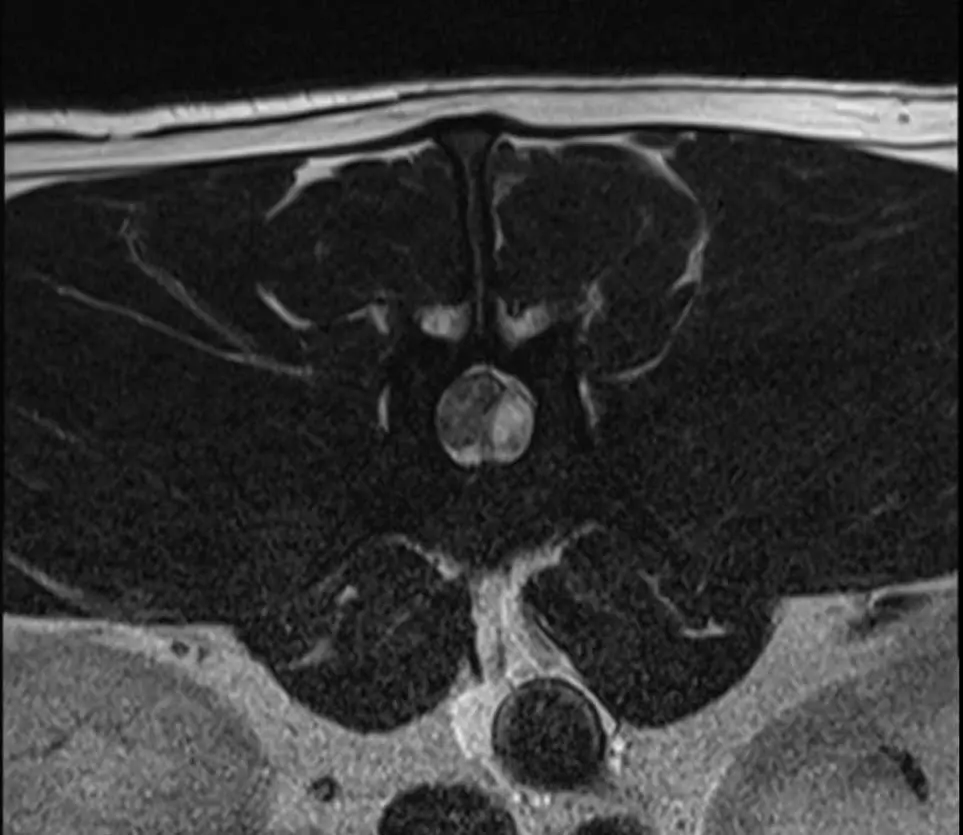

MRI

MRI is the most detailed form of imaging for spinal anatomy (Cooper et al, 2014). This modality can identify disc material, nerves, muscle, signs of haemorrhage and gives good soft tissue differentiation using different sequences (Dennis, 2011). It is seen as gold standard imaging, but duration of scanning time can be considerably longer in emergency situations and not all clinics have an on-site scanner.

The most common spinal condition (Holzman, 2023) is intervertebral disc disease (IVDD) – the herniation of the disc material that causes compression of the spinal cord leading to pain, weakness and paralysis (Dorn, 2022). It is the most common spinal condition.

Different disc herniation types can be classified into two subsections (Carver, 2016, Fenn 2020), as seen in Table 1.